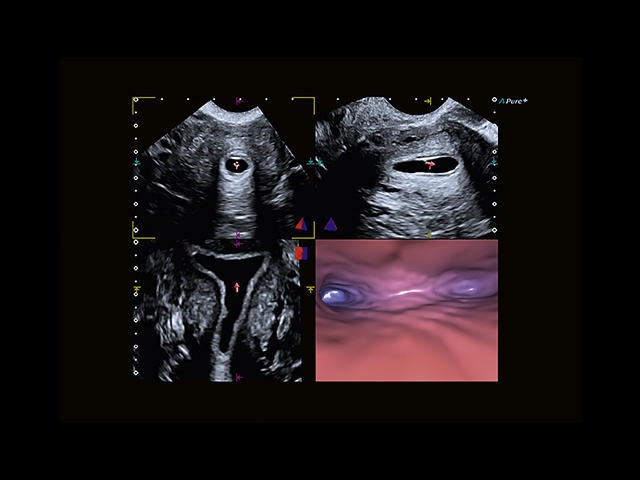

Обновленная версия легендарного УЗ-сканера. Стационарный аппарат экспертного класса Aplio 500 Toshiba NEW, визуализирует анатомические структуры в высоком разрешении. Модель позволяет выявить микрокальцификаты, новообразования, нарушения в работе сердца, сосудов и мышц. Присутствует функция виртуальной эндоскопии, 4D-сканирования, эластометрии тканей, УЗИ с контрастированием. За повышение качества изображения отвечают технологии ApliPure и Superb Microvascular Imaging. Первая задействует возможности пространственного и частотного кодирования, формирует цельный визуальный ряд с сохранением клинических маркеров. Вторая улучшает отображение микрососудистого русла, используя доплеровский эффект. Модель оснащена 21-дюймовым монитором, имеет 4 активных порта. Возможно подключение педиатрических, интраоперационных, лапароскопических и чреспищеводных датчиков.

• Fly Thru. Виртуальная эндосонография обеспечивает построение трехмерной модели полостей, протоков и сосудов в рельном времени, облегчает организацию инвазивных процедур и динамических исследований. Посредством Fly Thru можно установить шунты и стенты, проводить точные оперативные вмешательства.

Гинекология:

Да